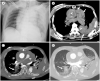

Sudden cardiac death is an unexpected death originating from the heart that occurs within an hour of the onset of symptoms. The main cause of sudden cardiac death is arrhythmia; however, diagnosing underlying structural heart disease significantly contributes to predicting the long-term risk. Cardiovascular CT and MR provide important information for diagnosing and evaluating structural heart disease, enabling the prediction and preparation of the risk of sudden cardiac death. Therefore, we would like to focus on the various structural heart diseases that increase the risk of clinically-important sudden cardiac death and the importance of imaging findings.